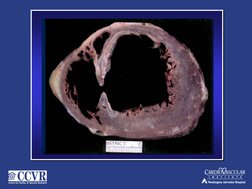

End-diastolic and end-systolic ventriculograms

Shawl,FA et al JACC 1989:14:967